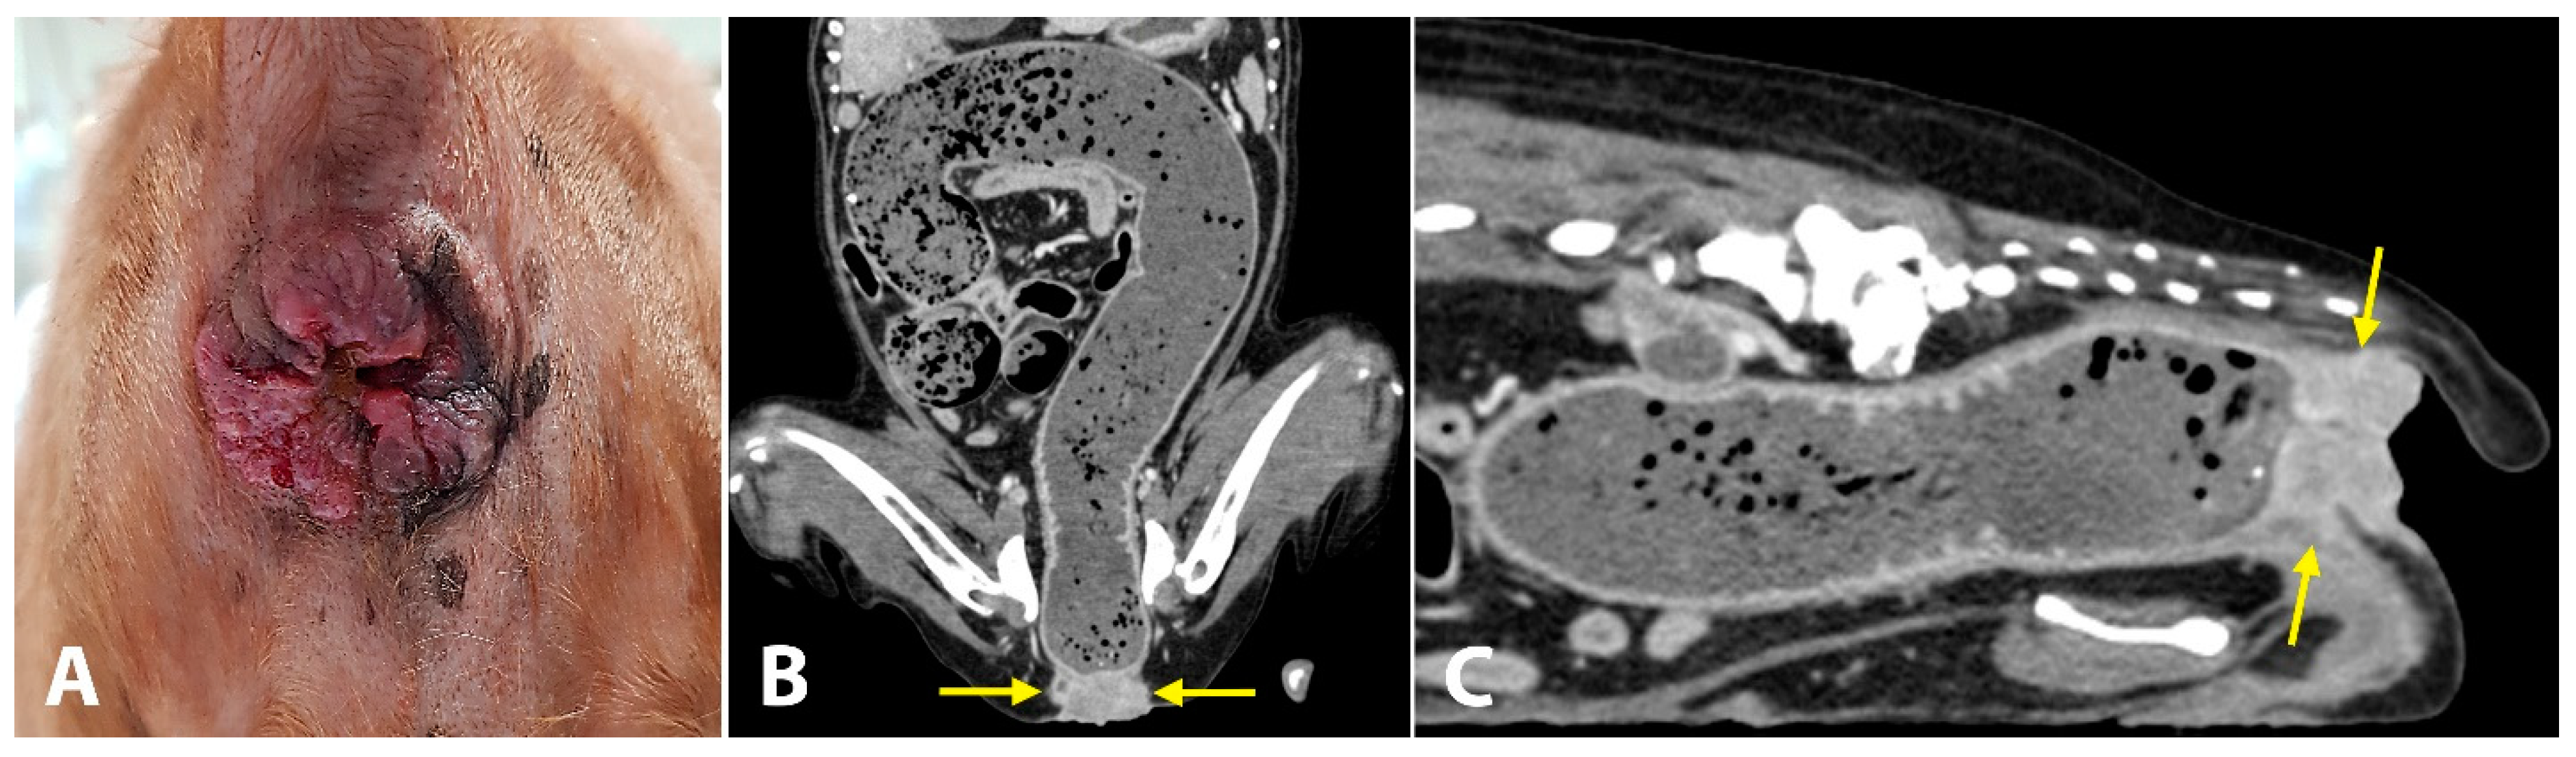

A 19-year-old spayed female English cocker spaniel dog weighing 8.7 kg was referred for evaluation of chronic inflammation of the anus, anal mass, and constipation. This anal disorder had been treated with oral medications (laxatives, antibiotics) and topical corticosteroids; however, for the last three weeks, these treatments had no effects on constipation. As the inflammation worsened and the mass became larger, the dog struggled more with defecation. The owners reported that, for the last 5 days, the dog showed severe constipation and became completely anorexic. On initial physical examination, the dog was depressed and had a body condition score of 3/9. The anus was covered with solid, ulcerative, and hyperplastic tissue (Figure 3A). The little finger could not be passed through the anus due to the severely narrowed and stenotic anorectal canal. While examinations were carried out, the dog continued to try to defecate but failed. Complete blood count and serum biochemistry tests revealed leukocytosis (16.86 K/μL; reference range, 5.05–16.76 K/μL), low hematocrit levels (32.2%; reference range, 37.3–61.7%), hypokalemia (3.2 mEq/L, 3.5–5.8 mEq/L), elevated alkaline phosphatase activity (402 UI/L; reference range, 46.2–337.2 UI/L) and elevated C-reactive protein levels (210 mg/dL; reference range, 0–35 mg/dL). Computed tomography (CT) was performed to evaluate the anorectal region and detect evidence of metastasis. The mass (14 × 34 mm) was completely blocking the anus (Figure 3B,C). Signs of metastasis were observed on CT. Popliteal, sacral, and iliac lymph nodes were abnormally enlarged. A solid mass was observed in both the liver (23.2 × 16.2 mm) and spleen (16.8 × 10.1 mm). The dog was diagnosed with anorectal cancer. Considering the possibility of metastasis, the owner decided to proceed with salvage surgery to resolve the anal blockage without any further treatment.

Figure 3. Photograph (A) and computed tomography (CT) images (B,C) of anal mass in a dog. (A) Solid mass with an ulcerative and hyperplastic surface at the anal region. (B,C) CT shows an anal mass (yellow arrows), completely blocking the passage of feces. The entire colon is severely dilated.